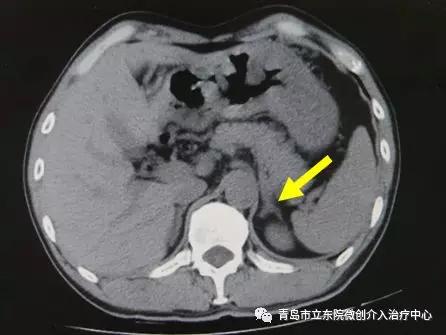

入院后检查发现:血钾低、血浆肾素正常、血醛固酮升高。CT示左侧肾上腺增生。

但全面的病因检查又有了新发现。肾动脉CT造影检查发现患者左侧肾动脉有严重狭窄。